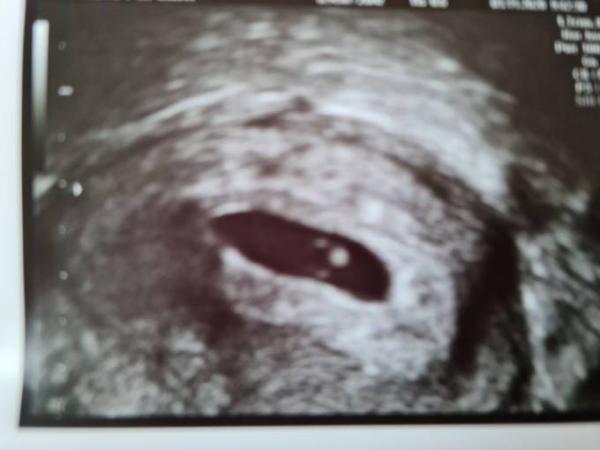

Hallo zusammen, Ich hatte heute früh meinen ersten FA Termin. Müsste irgendwas zwischen 5+4 und 6+0 sein. Man hat schön fruchthöhle mit dottersack und embryo gesehen und sogar schon herzaktion! Das hatte ich so früh gar nicht erwartet. In 4 Wochen habe ich den nächsten Termin. Ab nächster Woche bin ich dann im beschäftigungsverbot. Liebe Grüße!

Hier noch das Bild...